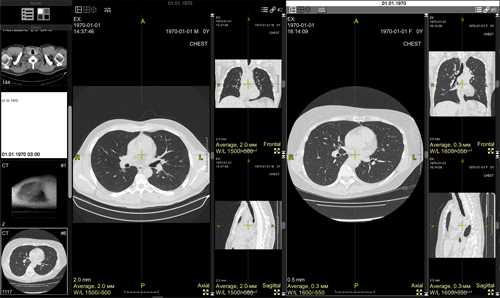

The screen will split into two parts:

The first part will contain the current study,

the second part will be about the next study in the Preview Bar